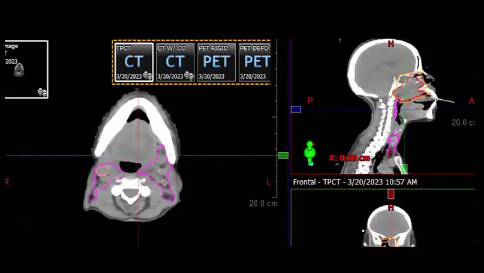

nasopharynx, MRI, PET, CT, NPX carcinoma, balloon procedure, right nasal pharyngeal carcinoma, 2A node, microscopic disease, T1, CLL, right parotid mass, squamous cell, right superficial parotidectomy, modified neck dissection, right temporal skin lesion excision, lymph node, ECE, bolus, dissecte...